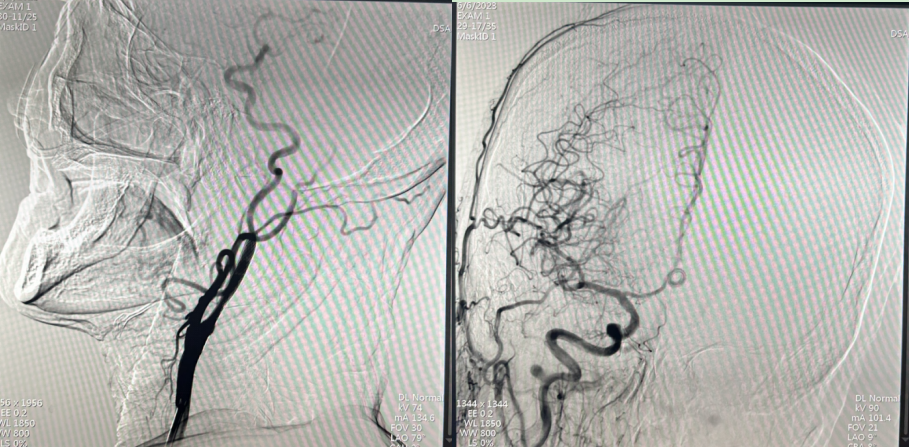

值班医师在接诊后迅速对患者进行评估,相关查体:体温36.2 ℃,脉搏 66 次/分,呼吸20次/分,血压 146/90mmHg,意识模糊,构音障碍,双眼向右侧凝视,无眼震,左侧鼻唇沟浅,伸舌左偏,左侧肢体肌张力增高,左上肢肌力0级,左下肢肌力2级,痛觉查体正常,共济运动查体不合作,左侧babinski征及Chaddock征阳性。术前评估:NIHSS评分11分,病前MRS评分0分,考虑大面积脑梗死可能,并在前循环大血管病变急诊介入时间窗内,检查无手术禁忌症,向患者家属交代病情,交代介入治疗的适应症及手术相关风险,患者家属签署知情同意,于22:40在导管室行主动脉弓全脑血管造影术,并准备行颅内动脉支架取栓术。脑血管造影术中发现患者责任血管为右侧大脑中动脉分支血管,不具备取栓条件,但右侧颈内动脉起始端重度狭窄,全脑血管造影评估患者侧支循环良好,结合患者症状、体征、发病时间及血管条件,介入团队紧急术前讨论,权衡获益风险,再次与患者家属沟通,行颈内动脉球囊扩张+支架植入术。

图一:支架植入术前